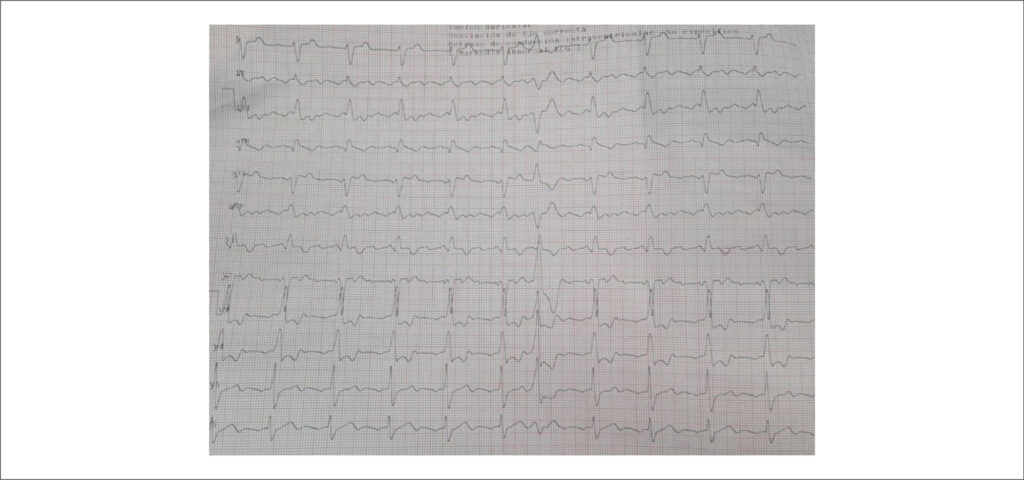

Síndrome de Lutembacher Associada à Hipertensão Pulmonar: A Importância do Diagnóstico Precoce para Viabilizar o Tratamento Cirúrgico

A síndrome de Lutembacher (SL) é definida pela presença concomitante de comunicação interatrial (CIA) e estenose mitral (EM). Embora seja uma condição rara, sua importância clínica decorre do impacto hemodinâmico significativo e da possibilidade de evolução precoce para hipertensão pulmonar (HP) irreversível.